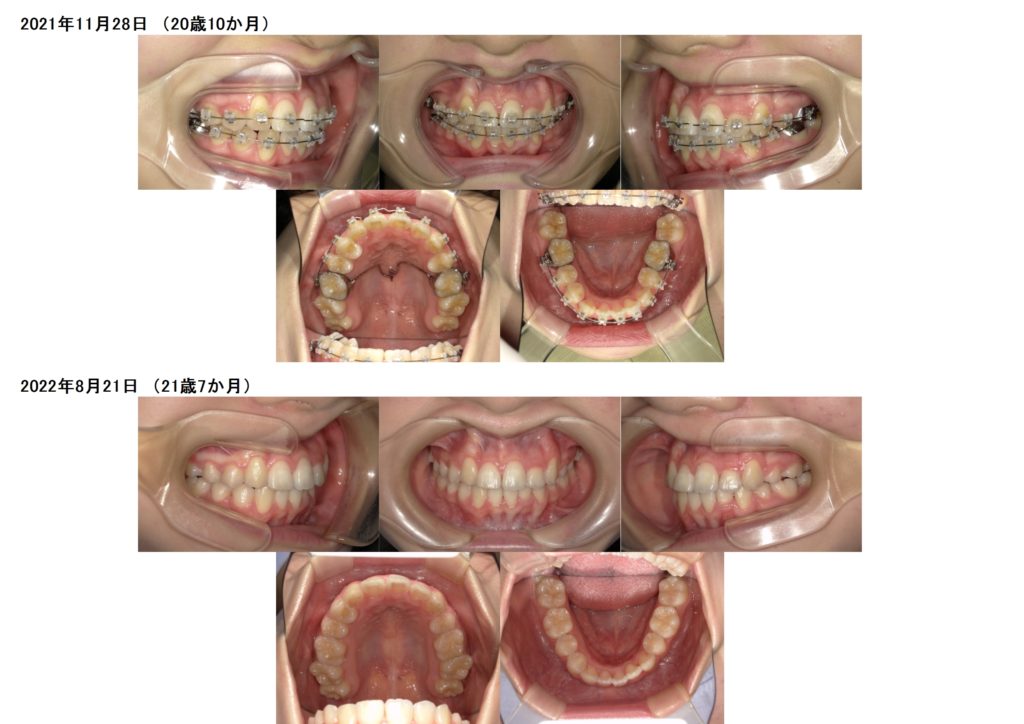

どんどん歯は動いていきます☆

とっても早いスピードですよね☺

最後に3カ月ほど、噛み合わせを整えるために顎間ゴムを使用しました。

とってもキレイに歯並び、噛み合わせが整いました。